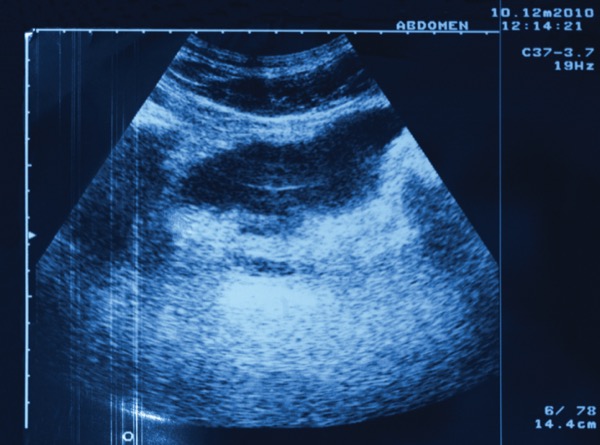

While “traditional monitoring strategies are invasive, require extensive preparation, often are not well tolerated by patients, and do not provide real-time results,” IUS is a point-of-care test that can be completed during a clinic visit, Dr. Krugliak Cleveland said.

According to Dr. Krugliak Cleveland, IUS enables tight disease monitoring and assessment of transmural healing. The STRIDE-II systematic review, which encompasses evidence- and consensus-based recommendations for treat-to-target strategies in adults and children with IBD, suggested that sonographic transmural healing is a future therapeutic target and that “the use of bedside ultrasound has revolutionized our ability to assess the degree of inflammation in IBD” (Gastroenterology 2021;160[5]:1570-1583).

But Dr. Dr. Krugliak Cleveland countered that “actually, the negative predictive value of intestinal ultrasound is very high, with sensitivity and specificity of IUS of 89% and 94.3%, respectively” [Inflamm Bowel Dis 2016;22(5):1168-1183]. “So, if you don’t see inflammation in a Crohn’s patient, you have high certainty that there is no active disease. Although air used to be a huge consideration, with current ultrasound image resolution and graded compression by the sonographer, you can see all of the bowel wall to submillimeter resolution.”